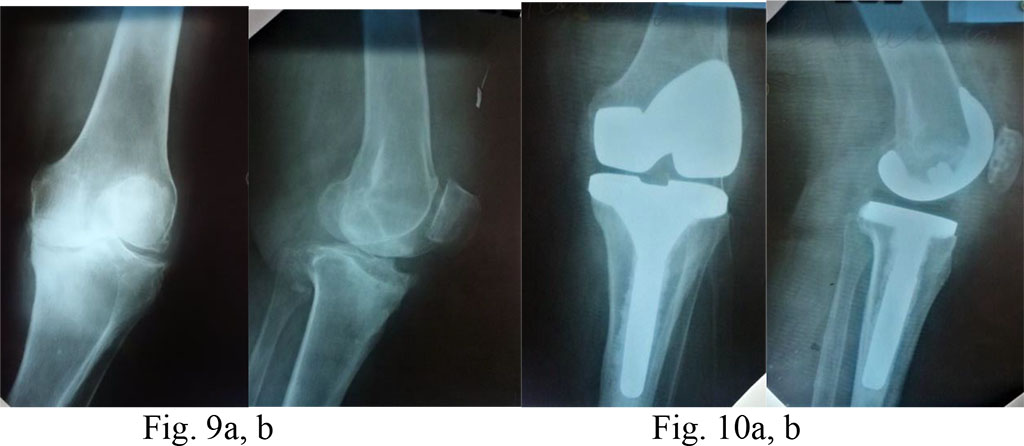

Diagnosis: knee osteoarthritis on the left, stage 4 according to Kellgren&Lawrence (1957); a posttraumatic lesion of the medial tibial process; varus deformity of the joint; expressed pain syndrome.

Surgical treatment: total arthroplasty of the right knee with an extended tibial component, CR method (PCL preserved) (Fig. 9a, b and 10a, b)